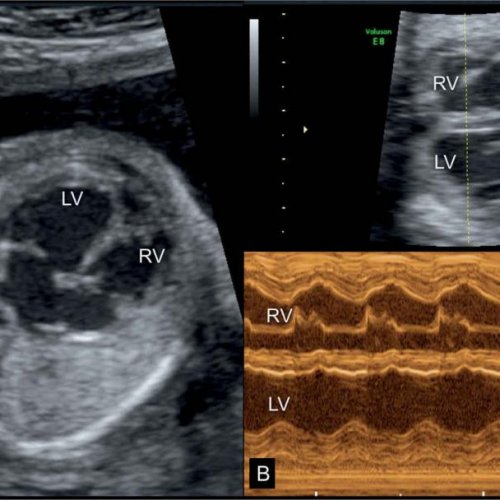

УЗИ сердца плода